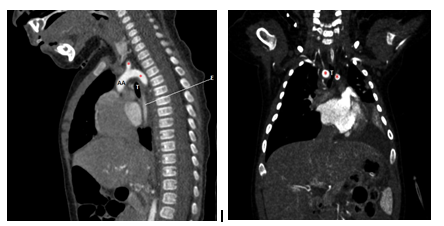

Figure 2 (A) Sagittal reconstruction of angiotomography showing the origin of the ascending aorta (AA) with two branches one right and one left in relation to the tracheal ring (*) B) Coronal reconstruction demonstrates the decrease in the caliber of the trachea ( T) with right and left indentation prior to the bifurcation of the main bronchi.

Figure 3 (A) sagital reconstruction of angiotomography in a lower cut, where the origin of the ascending aorta (AA) and the beginning of one of the branches that make up the vascular ring (*) can be seen. Note the decrease in the caliber of the trachea (T) and the esophagus (E) which is occupied by an orogastric tube, with a descending aorta (DA) of trajectory and usual caliber. B) axial cut of angiotomography where the vascular ring is clearly evident (*), conditioning compression of trachea (T) and esophagus (E) observing hyperdense material in relation to central venous catheter (CVC).